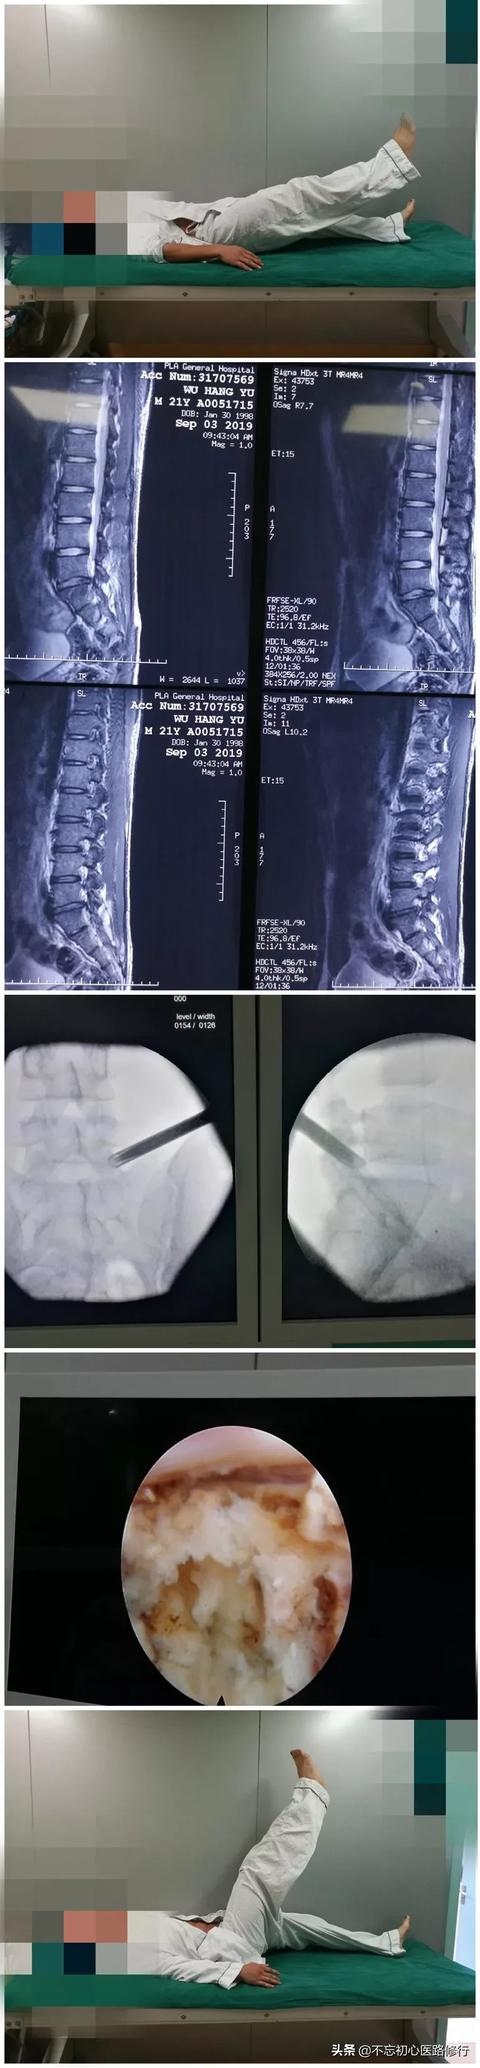

第一に、診断が正しいこと、つまり臨床症状と画像が一致していること、第二に、痛みの原因が腰椎椎間板ヘルニアによるものであり、筋筋膜病変などの軟部組織の病理によるものではないことです。

現在、腰椎椎間板ヘルニアは2つのメカニズムによって腰痛を引き起こすと考えられている。1つは圧迫メカニズム、つまり椎間板の突出した髄核が脊髄神経根を直接圧迫するメカニズムであり、もう1つは炎症介在メカニズム、つまり線維輪の破裂によって引き起こされ、椎間板の突出した髄核が炎症メディエーターを放出し、脊髄神経根を刺激して痛みを引き起こすメカニズムである。

腰椎椎間板ヘルニアの手術は、現在、低侵襲手術と開腹手術の2種類があります。低侵襲手術には、高周波、プラズマ、椎間孔内視鏡などがあります。前二種類の手術は、より外傷が少なく、回復が早い疼痛科で行われますが、椎間板ヘルニアの小さい症例に限られ、過去の経験によると、急性発症時の鎮痛効果はまだ非常に良好です。

椎間板ヘルニアが大きい場合、椎間孔径手術の効果が良い。 椎間孔径手術の切開は小さく、通常7mm程度で、傍椎骨筋や靭帯を破壊せず、出血が少なく、脊椎の安定性に影響がなく、術後は神経圧迫が除去されるため、痛みの症状が早く緩和される。開腹手術は腰椎椎間板ヘルニアに腰椎変性症、骨棘、脊柱管狭窄症、神経根管狭窄症、靭帯石灰化などを伴う患者や、明らかに腰椎が不安定な患者が対象です。

適応症が正しく選択されれば、手術の成功率は90%か95%以上になる。適応症が適切に選択されなければ、成功率は基本的に60%前後である。手術の具体的な適応は、患者が最初に腰部痛、両下肢のしびれ、直脚挙上テスト陽性、両足母指背屈筋の著しい筋力低下、患者の腰部機能的活動の著しい制限を訴える場合である。